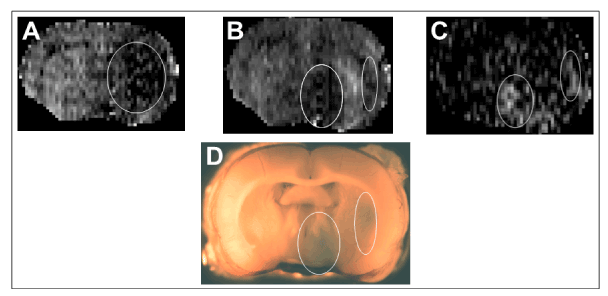

Microvascular status

Extravascular enhancement of Gd-DTPA was observed in at least one ROI in all experiments, confirming localized BBB opening after reperfusion (Figure 1C). Macroscopic examination of the corresponding 2 mm thick brain slices showed blue coloration indicating subsequent EB leakage as well in these regions (Figure 1D). An examination of images from contralateral hemisphere showed intricately interconnected vascular networks (Figures 2A1-C1). Microvessels were filled with plasma labeled by EB that fluoresced red and FITC-RBCs were seen as green circles or ovals within the plasma (Figures 2A1-2C1). The cortex seemed to display relatively denser and more complex vascular organization per visual evaluation, but this needs to be confirmed by future quantitation. The blood smear preparation showed a population of intact, FITC-labeled RBCs (Figure 2D). The adaptive deforming capacity of RBCs during their transit could be discerned by a comparison of the circular cells seen in 2D with the intravascular FITC-RBCs shown magnified in Figures 2A-2, 2B-2 and 2C-2 that appear either oval, oblong or otherwise squeezed, very likely to conform to the microvascular lumen. Unlabeled RBCs were perceived as dark gaps in the red EB fluorescence.

Figure 1. A typical set of MR images and the corresponding Evans blue stained brain section from an experiment. From left to right, the first two are the coronal CBF images of the brain during occlusion (A) and reperfusion (B) and the third is a T1 subtraction image showing the region of contrast enhancement (C).The dark region outlined in the right hemisphere in A is ischemic. It is seen that following reperfusion cerebral blood flow is restored in the center of this lesion flanked by two separate regions with sustained low blood flow (bright pixels in the middle of the two ovals in B). In the T1 subtraction image, two distinct regions of contrast enhancement (two ovals in C) indicating ischemia-induced acute blood-brain barrier opening are visible. These two ovals spatially correspond with the two regions with low blood flow shown in the reperfused brain in the middle panel. The 2 mm brain vibratome slice corresponding to the MR images is also shown (D) wherein blue regions of EBA leakage are visible on the ipsilateral side (oval outlines in D that spatially correspond to the 2 ovals in C).